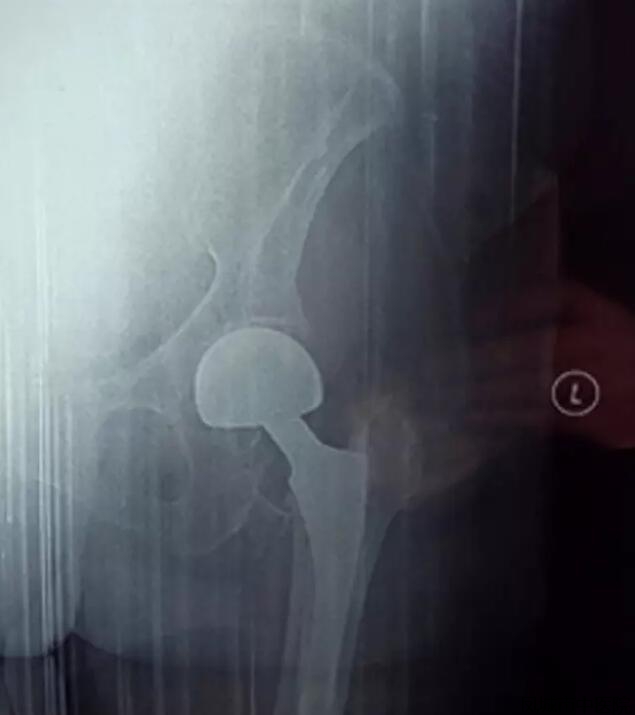

该患者,女性,86岁,干活时不慎摔倒,致左股骨粗隆间粉碎性骨折并股骨颈骨折来院。

老年股骨粗隆间骨折是比较难处理的骨折,不手术、卧床时间长、死亡率高,行关节置换,能让老人尽快离床活动,减少并发症的发生。但该患者年龄较大,心肺功能较差,并合并其他内科疾病,手术、麻醉风险较大.

骨伤科经内科、麻醉科会诊,围手术期管理,充分调整心肺功能,经过充分的术前准备,顺利完成了加长柄人工股骨头置换术。术后无各种并发症的发生,术后恢复良好,术后1周扶拐下地行走。